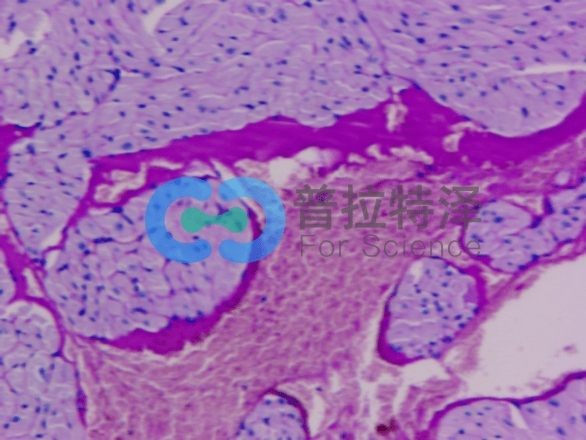

首先,我們來了解PAS染色的基本原理。它利用過碘酸將細胞中的多糖類物質氧化,再通過雪夫試劑與氧化后的多糖結合,形成特征性的紅色或紫色沉淀。這種沉淀能夠清晰地顯示出細胞中的多糖類物質分布和含量,從而幫助我們了解細胞的代謝狀態(tài)和功能特點。

[圖1]

在第二個層次,我們將探討PAS染色實驗在細胞結構與功能研究中的應用。多糖類物質在細胞中扮演著重要的角色,它們不僅是細胞壁和細胞膜的主要成分,還參與細胞的能量代謝和信號傳導等過程。因此,通過PAS染色實驗,我們可以觀察到細胞中多糖類物質的分布情況,進而推斷出細胞的生理狀態(tài)和功能特點。這對于研究細胞的生長、分化和凋亡等過程具有重要意義,也為疾病的診斷和治療提供了重要的依據(jù)。